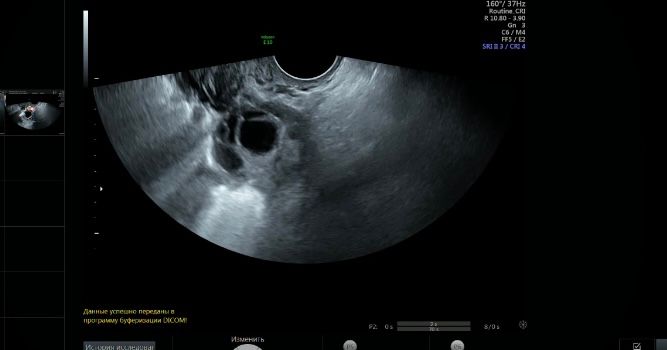

Фолликул или жёлтое тело?

Да , такие кровотоки у желтого тела

По кровотоку ЖТ. У меня узистка перепутала ЖТ и ДФ 🤦‍♀️, цикл оказался пролётным, кровоток был совершенно другой, а у вас отличный 👍